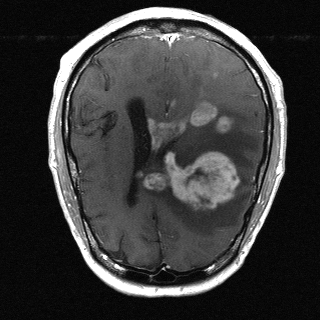

This article presents a novel undersampled magnetic resonance imaging (MRI) technique that leverages the concept of Neural Radiance Field (NeRF). With radial undersampling, the corresponding imaging problem can be reformulated into an image modeling task from sparse-view rendered data; therefore, a high dimensional MR image is obtainable from undersampled $k$-space data by taking advantage of implicit neural representation. A multi-layer perceptron, which is designed to output an image intensity from a spatial coordinate, learns the MR physics-driven rendering relation between given measurement data and desired image. Effective undersampling strategies for high-quality neural representation are investigated. The proposed method serves two benefits: (i) The learning is based fully on single undersampled $k$-space data, not a bunch of measured data and target image sets. It can be used potentially for diagnostic MR imaging, such as fetal MRI, where data acquisition is relatively rare or limited against diversity of clinical images while undersampled reconstruction is highly demanded. (ii) A reconstructed MR image is a scan-specific representation highly adaptive to the given $k$-space measurement. Numerous experiments validate the feasibility and capability of the proposed approach.